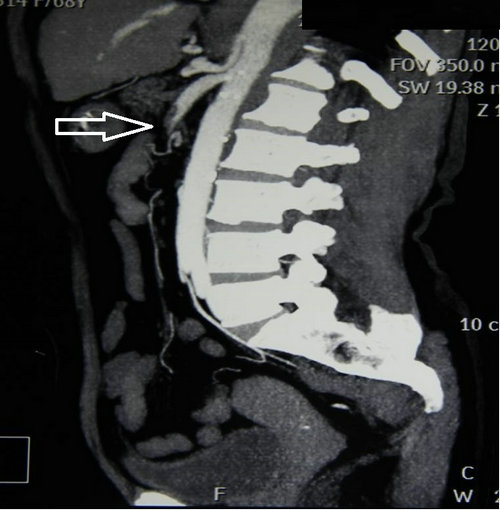

由于患者年龄大,冠心病、房颤20多年,基础情况差,术前请心内科关李华副主任及手术室闵娜医师前来会诊,给予制定围手术期处理意见。手术麻醉由胡强夫主任亲自进行,王兵副院长主刀。手术开始后发现肠管已经缺血发绀,幸运的是诊治及时,还未出现坏死迹象,腹腔也没有腹水。将肠系膜上动脉游离出来,取栓管取出的血栓将近10cm。缝合血管恢复血流后,肠管立即恢复红润,蠕动也明显改善。

急性肠系膜上动脉栓塞是由于栓子进入肠系膜上动脉造成阻塞所致,发病凶险,死亡率极高,最高可达88%—98%,症状表现为“Bergan三联征”:①突发腹部剧烈疼痛,药物不能缓解,早期腹软不胀,肠鸣音活跃,症状与体征不符;②器质性或并发房颤的心脏病,如房颤、风湿性心脏病、感染性心内膜炎、近期心梗病人;③胃排空障碍表现如腹泻、血便。该病的诊断非常困难,误诊率高达90%—95%,往往以阑尾炎、急性胃肠炎等疾病误诊,耽误了最佳治疗时间。肠管对缺血的耐受时间约12小时,尽早确诊并手术是降低死亡率的关键,患者肠道还有修复的可能性。缺血时间过长的患者肠道坏死,大量的肠毒素吸收、大量液体渗出导致患者很快出现中毒性休克,严重威胁生命。手术需要将肠道切除,导致“短肠综合征”。这类病人由于缺乏足够的肠管吸收营养,需要支付高额的全静脉营养费用,严重影响患者的生活质量。